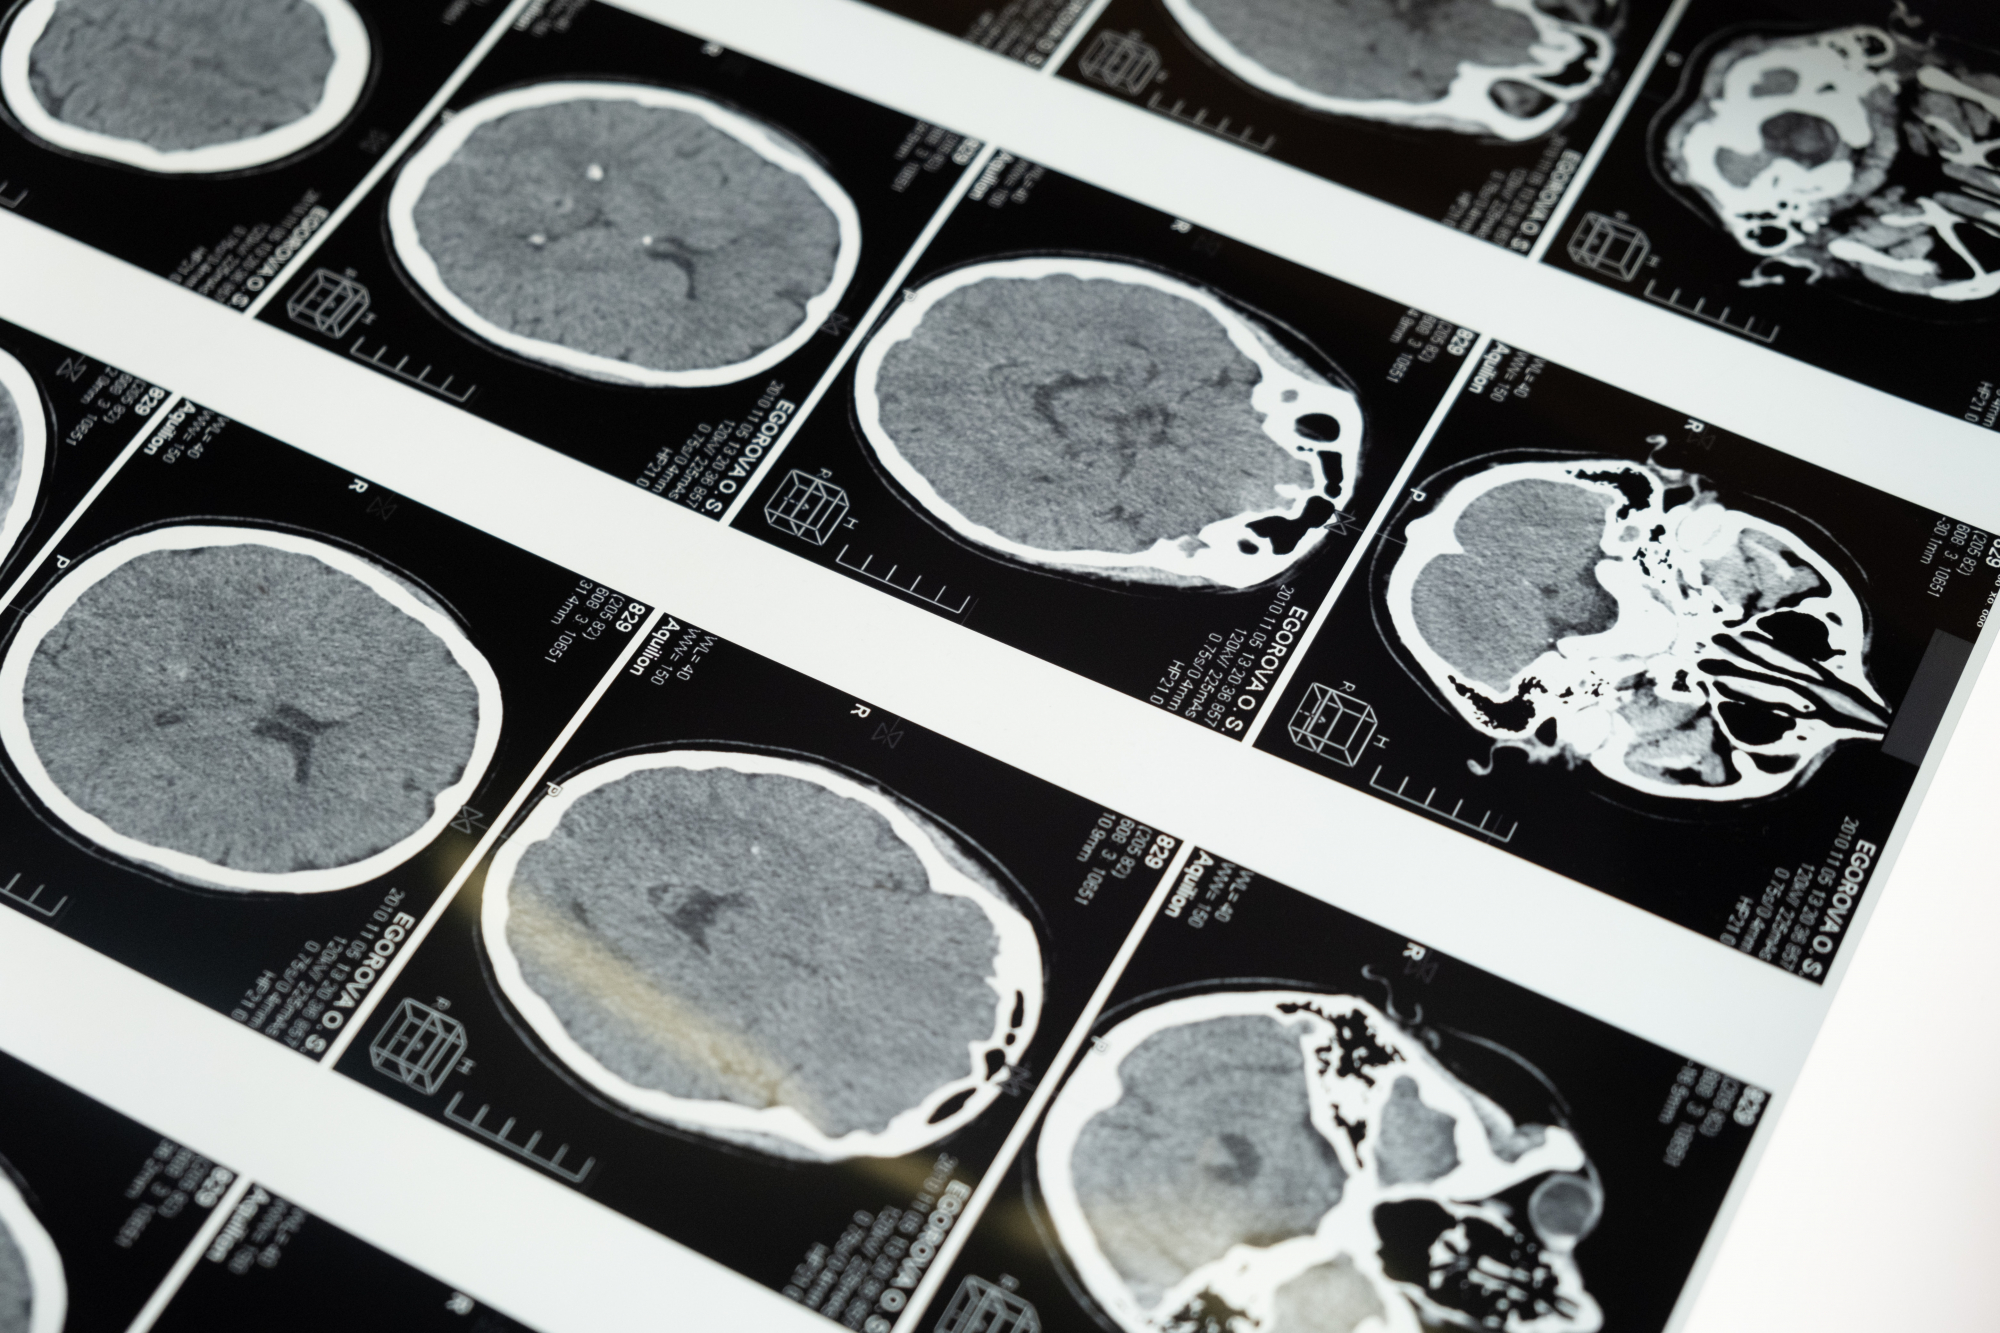

Η Gianna επισκέφτηκε νευρολόγο τον Νοέμβριο του 2022 και μετά από μία σειρά εξετάσεων οι γιατροί ανακάλυψαν ότι δεν υπήρχε ηλεκτρική δραστηριότητα στον δεξιό κεντρικό λοβό.

Είχε μόλις διαγνωστεί με άνοια.